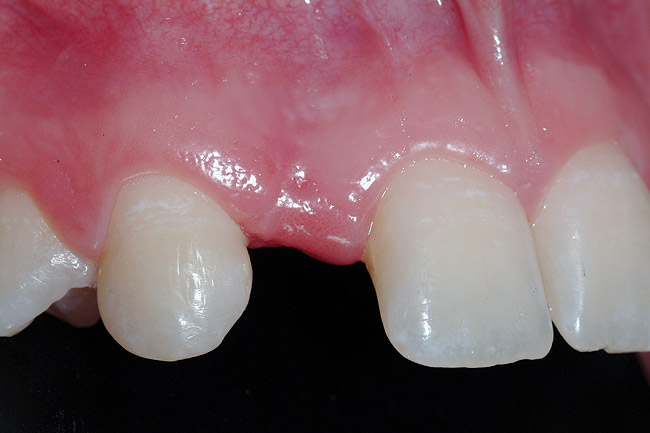

A 19-year-old non-smoking female presented for tooth replacement at the maxillary right and left lateral incisors, which were congenitally missing (Figure 1). The post-orthodontic result was adequate for the placement of 3-mm one-piece small-diameter implants. The preoperative radiographs can be seen in Figure 2 and Figure 3. The pretreatment clinical view in Figure 4 and Figure 5 shows the small intertooth space present in the lateral incisor areas. One of the most challenging tasks with congenitally missing lateral incisor cases is to create an acceptable soft tissue emergence profile from a crestal profile that is flat from the mesial of the canines to the distal of the centrals (Figure 4 and Figure 5). After pretreatment planning which consisted of a complete medical and dental history, radiographic analysis, and upper and lower study models mounted by a facebow transfer technique, the fabrication of a TempStent II surgical guide was completed. Figure 6 and Figure 7 show the occlusal view of the TempStent II guide on the study cast and in the oral cavity, respectively.

Figure 4  Pretreatment clinical view, right lateral incisor.

Figure 4

Figure 5  Pretreatment clinical view, left lateral incisor.

Figure 5